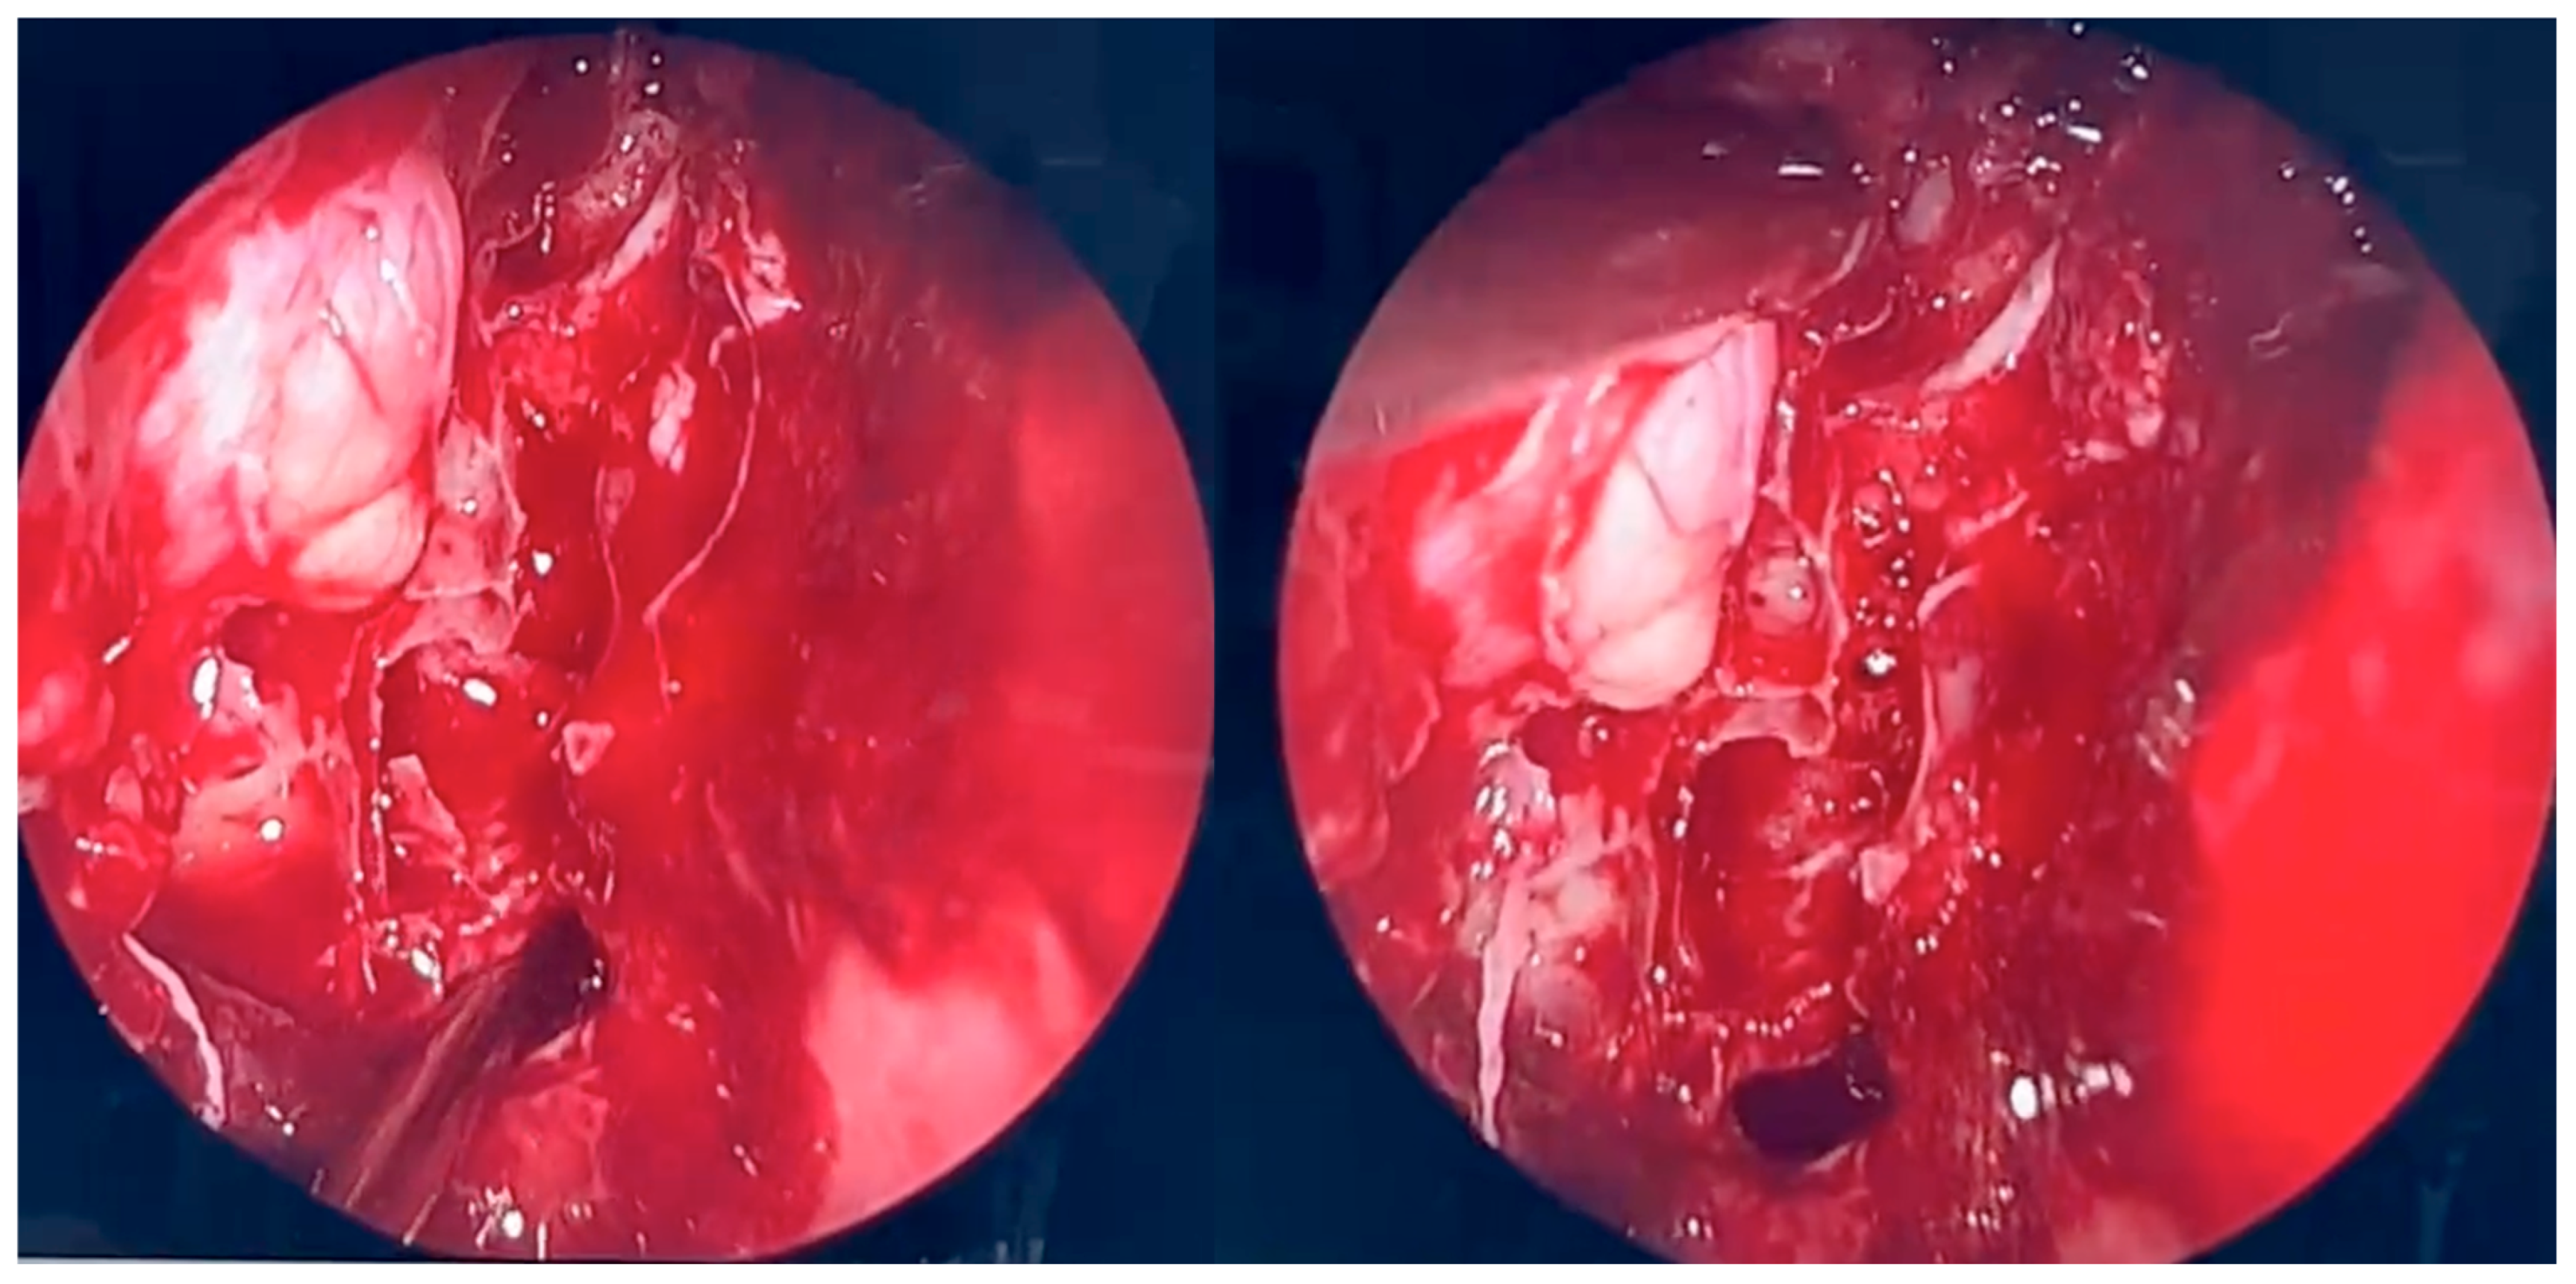

2.5. Second Surgical Procedure

During the second endoscopic procedure, significant postoperative anatomical alterations were observed, including extensive scarring and multiple synechiae. A defect of the medial orbital wall was identified. The underlying bone was visualized and found to be covered only by periosteum. Using a diamond burr, a portion of the bony boundary of the frontal recess was carefully removed to create a surgical access route toward the lesion previously identified on CT and MRI imaging. The lesion was located in the superomedial quadrant of the right orbit, between the medial and superior rectus muscles and adjacent to the retrobulbar segment of the optic nerve. The orbital periosteum was incised, and orbital fat was gently displaced to access the lesion. The pathological tissue was successfully removed and sent for histopathological examination. A nasal dressing was applied to complete the procedure.

Figure 4. Endoscopic surgery: intraoperative view after removal of fungal infiltration to the level of the skull base. Opening of the sphenoidal sinus seen inferiorly (6 o’clock position). The upper-left part of the picture (11 o’clock position) shows the site of orbital periosteum incision with partial herniation of orbital fat into the ethmoid cavity. Two images obtained from the same projection.

Figure 5. Endoscopic surgery: intraoperative view of the right maxillary sinus after removal of fungal masses. Opening of the sphenoidal sinus visible on the right (4 o’clock position).